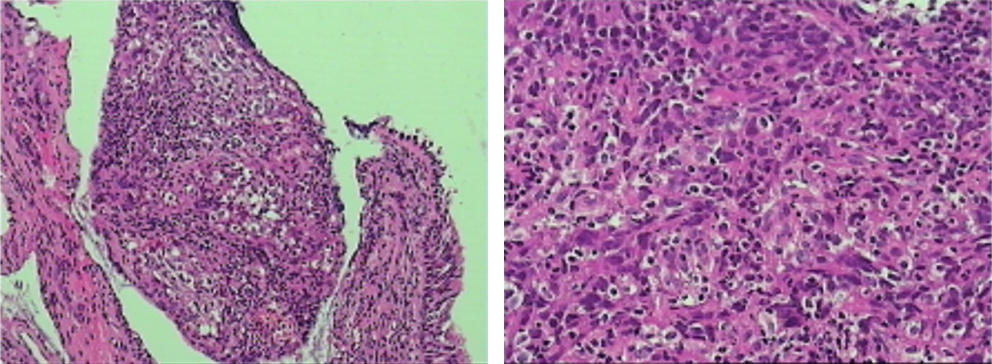

患者于2018-12-26、2019-01-19分别行第1-2周期TC方案(紫杉醇脂质体+卡铂,每3周1次),患者基线和化疗后肿瘤标志物变化如图3所示,肺和肝脏病灶变化影像如图4所示,2019-02-18复查CT提示肺部病灶稳定(缩小),肝脏病灶增多增大,总体疗效评价疾病进展(PD)。

2019-02-19、2019-03-14行二线贝伐珠单抗+多西他赛化疗(贝伐珠单抗+多西他赛,每3周1次)。2019-03患者开始出现腰部疼痛,考虑为L1椎体骨转移导致,2019-03-19开始行腰骶部局部放疗,2019-04-04复查CT结果如图5所示,肺部病灶稳定(部分缩小),肝脏病灶增多增大、T9-T12椎体新发转移瘤,总体疗效评价(PD)。

患者初治时行PD-L1(22C3)检测提示PD-L1高表达为95%,故建议患者行三线免疫治疗。由于药物可及性,患者综合考虑后,选择信迪利单抗。患者于2019-04-04、2019-04-26、2019-05-18分别行第1~3周期免疫联合化疗三线方案(信迪利单抗+白蛋白紫杉醇 ,每3周1次)。2019-05-18复查肺部CT如图6所示,2019-05-18复查CT:肺部病灶较前明显缩小,阻塞性肺炎较前好转、肝脏病灶较前明显缩小。T2、T9-L2椎体及L2左侧附件多发骨转移同前。

图6 2019-05-18复查胸腹部CT提示肺部病灶较前明显缩小,阻塞性肺炎较前好转、肝脏病灶较前明显缩小。T2、T9-L2椎体及L2左侧附件多发骨转移基本同前

患者于2019-06-12、07-08继续行第4-5周期三线方案(信迪利单抗+白蛋白紫杉醇 ,每三周一次),2019-07-26复查胸腹部CT提示,肺部病灶较前明显缩小,肝脏病灶较前明显缩小。T2、T9-L2椎体及L2左侧附件多发骨转移同前(图7)。患者肿瘤标志物也基本呈现下降趋势(图8),疗效评价为(PR)。

图7 2019-07-26复查胸腹部CT提示,肺部病灶较前明显缩小,肝脏病灶较前明显缩小。T2、T9-L2椎体及L2左侧附件多发骨转移同前